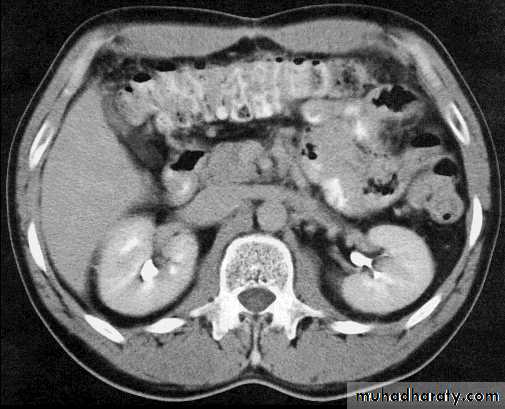

Comparisons

Cross sectionCAT image

abdomen